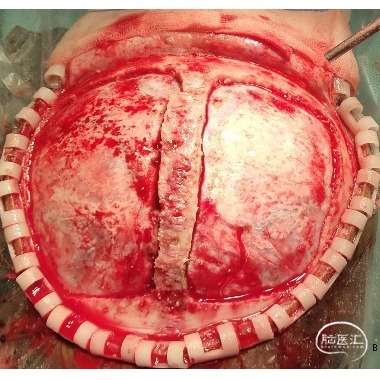

本例患儿肿瘤位于双侧额顶叶,大脑镰旁,增强扫描呈明显环形强化,提示肿瘤血运丰富。患儿年龄小,体重低,相对血容量少,如何控制术中出血是手术成功的关键。而术后肢体瘫痪或瘫痪加重是手术的主要并发症,中央沟静脉损伤、胼周动脉损伤、中央沟局部皮层损伤、癫痫、血肿以及脑水肿加重是其常见原因。术前脑血管造影有助于判断肿瘤与周围血管、组织的位置关系,明确上失状窦有无闭塞,对手术的切口设计有重要的参考价值及避免术中损伤不易发现的血管及组织。

本例患者术前脑血管造影提示瘤体主要由双侧大脑前动脉终末分支供血,造影静脉期瘤体显影明显,因此我们选择先采用神经介入技术超选部分主要供瘤动脉予弹簧圈栓塞,减少瘤体的供血。之后再行开颅探查双侧额顶叶占位性病变切除术。

儿童颅内肿瘤多血运丰富,且儿童本身体重低,血容量较少,开颅术中对于出血的控制尤为关键。术前尽可能的明确肿瘤与周围血管、组织间的关系,切口设计既要能够安全、彻底地切除肿瘤,又要避免无效开颅和无效脑暴露,增加不必要的医源性创伤,不可过分强调小骨窗,当肿瘤血运丰富,有条件时尽可能行供瘤血管栓塞,减少术中切肿瘤时出血。